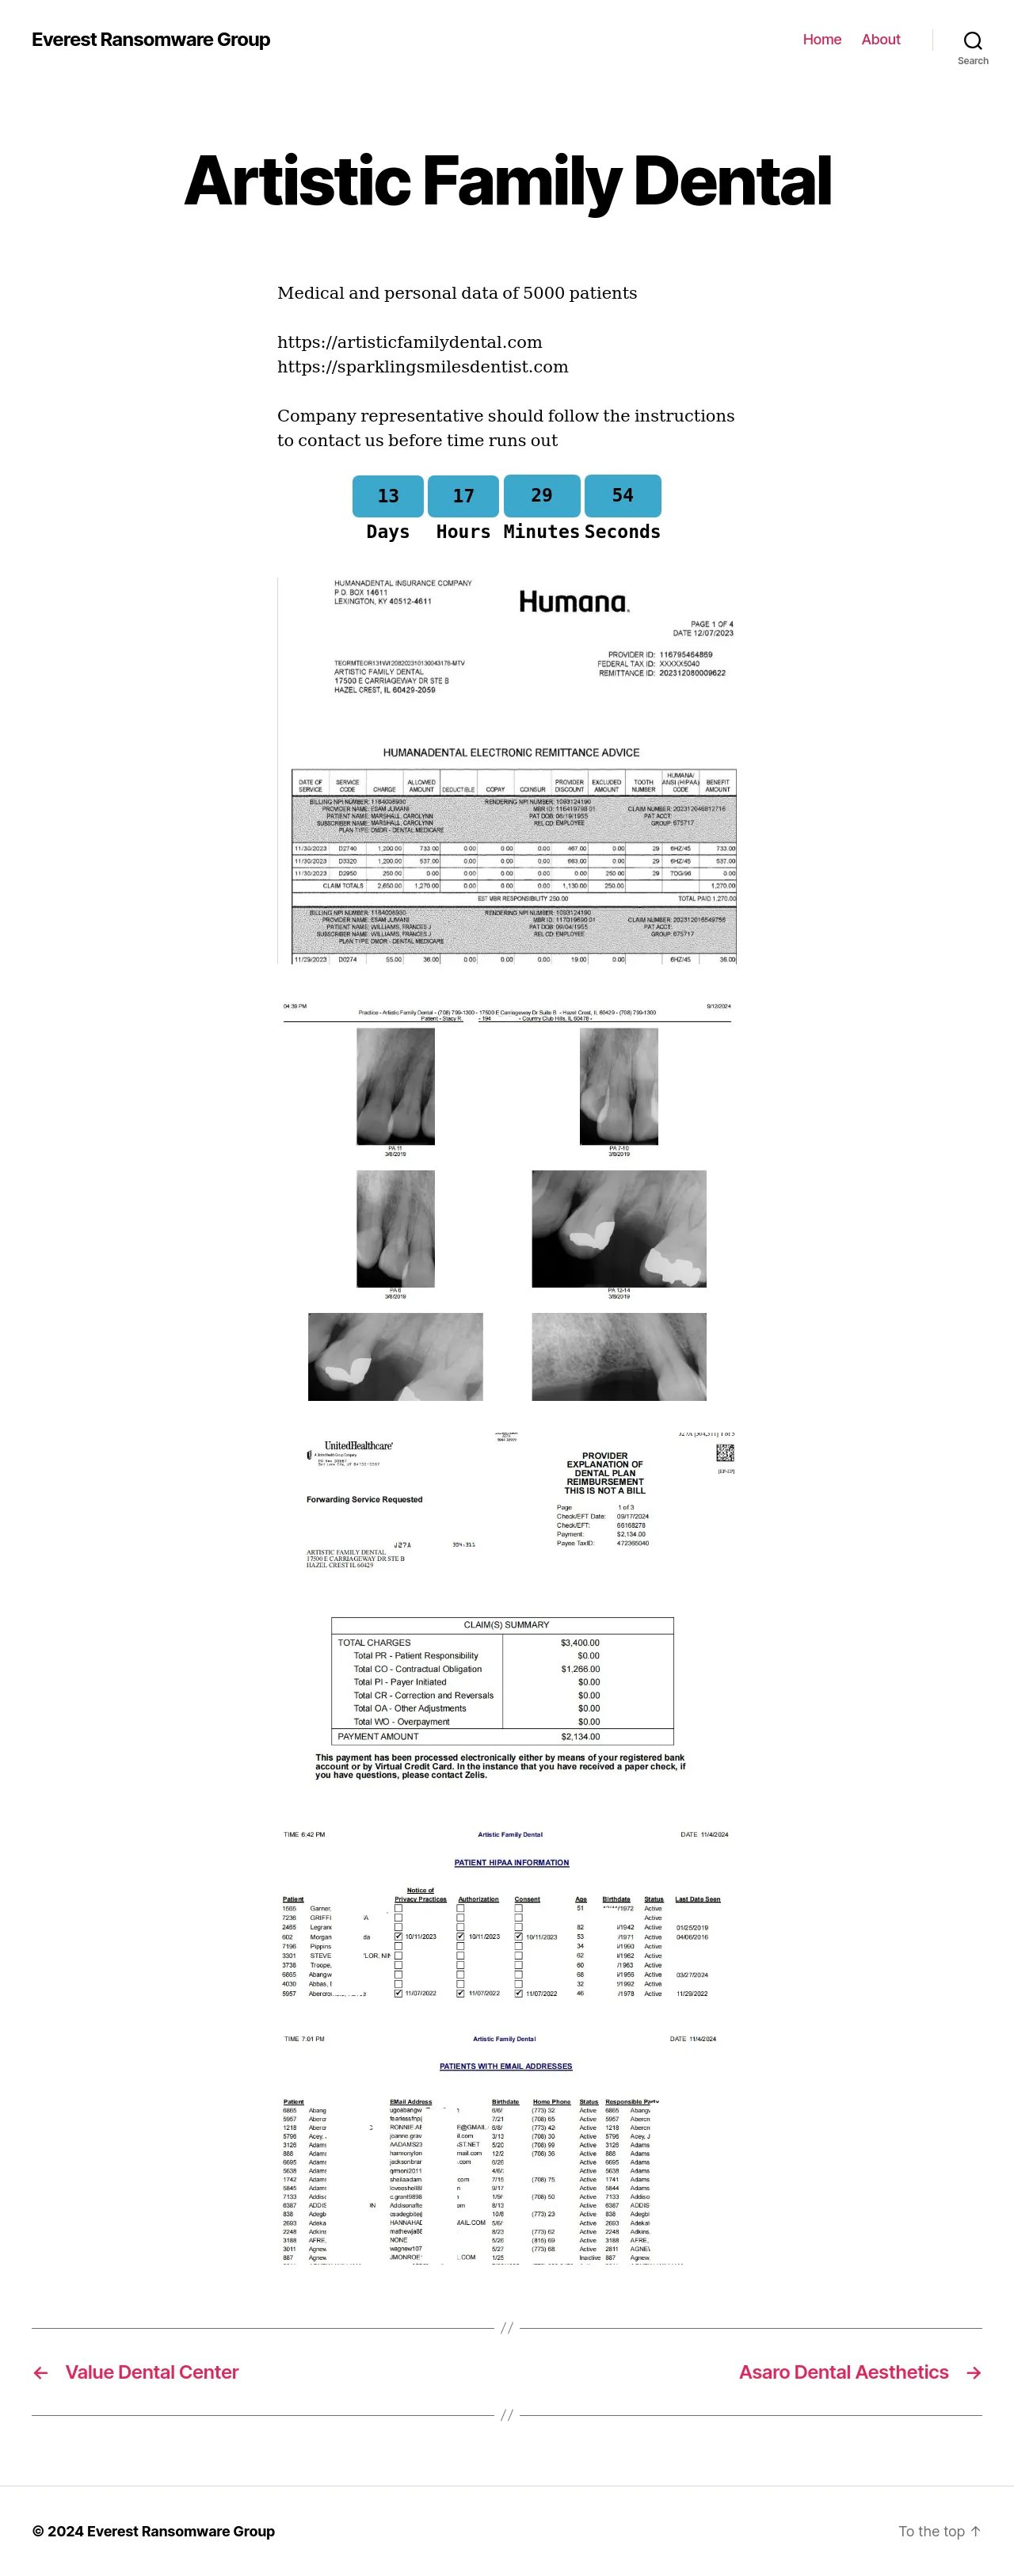

Artistic Family Dental |

Medical and personal data of 5000 patients https://artisticfamilydental.comhttps://sparklingsmilesdentist.com Company representative should follow the instructions to contact us before time runs out |